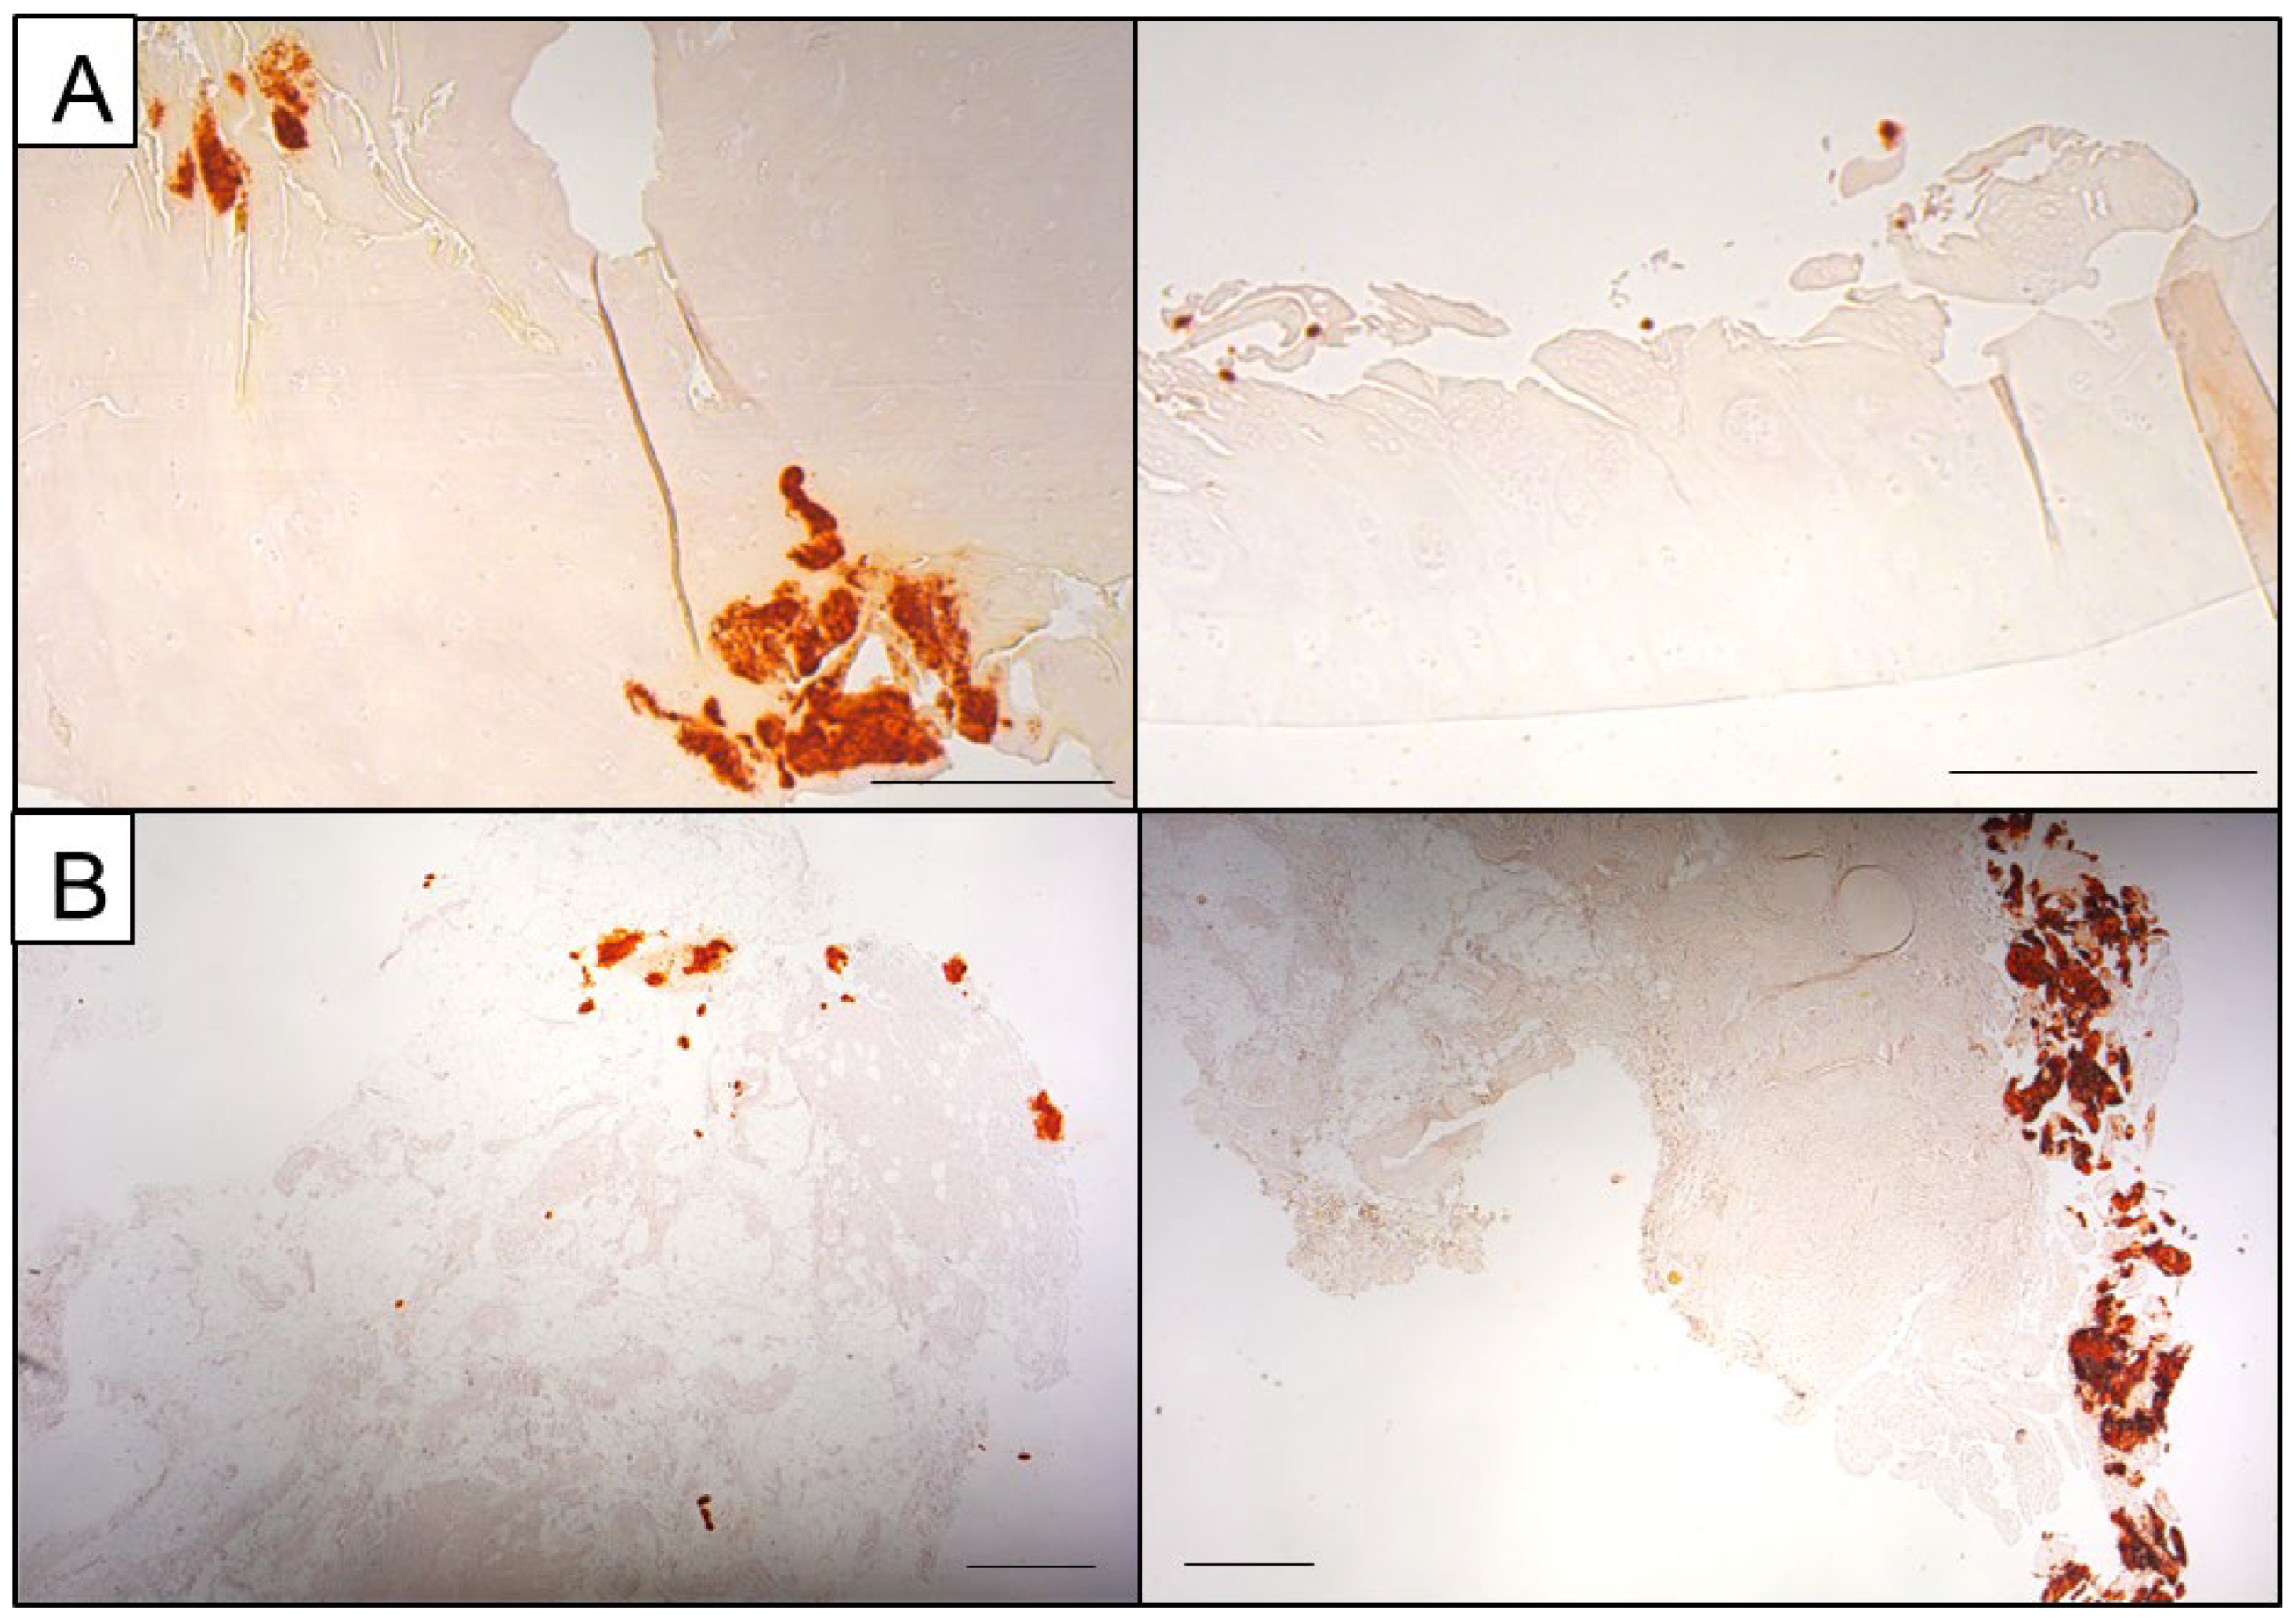

Figure 2.

Representative Von Kossa images of partly calcified joint tissue. (A) Calcifications can be embedded within cartilage tissue and located in the deeper layers exhibiting a powdery appearance (left panel) or presenting as calcified chunks located loosely at the chondrocyte surface (right panel, scale bars: 500 µm). (B) Synovial membrane specimens can exhibit both smaller calcifications and bigger calcified chunks that are integrated into the surrounding tissue or loosely presented aside (scale bars: 500 µm).

The images generated by the SE detector are displayed in shades of grey. This, in combination with the high minimum magnification of 50×, aggravates the difficulties in orientation on the sample, even with Von Kossa staining as a template on a separate serial section. Therefore, a BSE detector which, in simplified terms, renders areas with higher atomic numbers brighter, can be a great help in finding the calcified regions of interest (ROIs). The BSE detector greatly facilitates the search for calcified areas, as the search is performed visually and within live imaging. Figure 6 shows both imaging methods in direct comparison for a representative cartilage section. The BSE images (right side) clearly show calcification in lighter tones while the SE image (left side) has multiple lighter spots due to electric charge, especially at the rim of the tissue. This method is not only restricted to cartilage but can also be applied to synovial membrane sections (Figure 6B).

Comparison between SE and BSE image of partly calcified cartilage (A) and synovial membrane (B). Left: SE, right: BSE. The BSE images clearly show calcification in lighter tones (red markings) while the SE image displays multiple lighter spots due to electric charge, especially at the rim of the tissue, complicating the search for ROIs and the overall visibility.